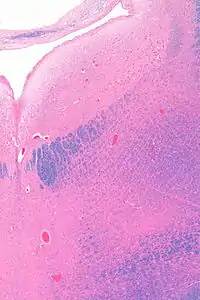

![]() Micrograph showing the locus coeruleus. HE-LFB stain. | |

Anatomy

The locus coeruleus (LC) is located in the posterior area of the rostral pons in the lateral floor of the fourth ventricle. It is composed of mostly medium-size neurons. Melanin granules inside the neurons of the LC contribute to its blue colour. Thus, it is also known as the nucleus pigmentosus pontis, meaning "heavily pigmented nucleus of the pons." The neuromelanin is formed by the polymerization of norepinephrine and is analogous to the black dopamine-based neuromelanin in the substantia nigra.

In adult humans (19-78) the locus coeruleus has 22,000 to 51,000 total pigmented neurons that range in size between 31,000 and 60,000 μm3.[4]